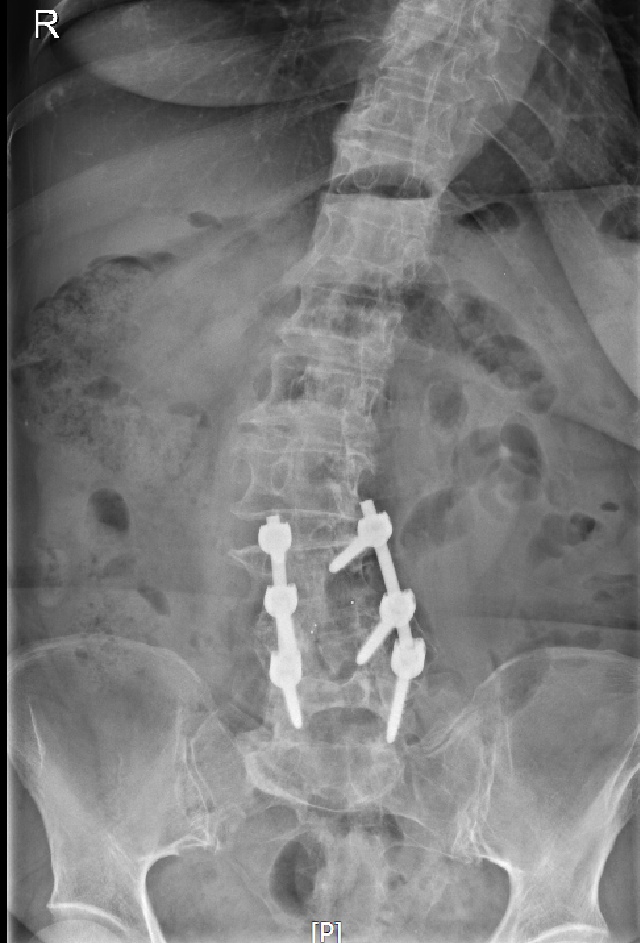

术前X-RAY显示严重脊柱侧弯,椎管内肿瘤

“这种情况,常规会进行开放手术,治疗刀口有20公分左右,脊柱内需要置入10-12枚螺钉,对于高龄、体弱的病人,存在创伤大、出血多、恢复慢等缺点。”曹鹏医生介绍,若单纯做脊柱肿瘤切除,患者已经侧弯的脊柱会加重,严重影响患者预后康复。